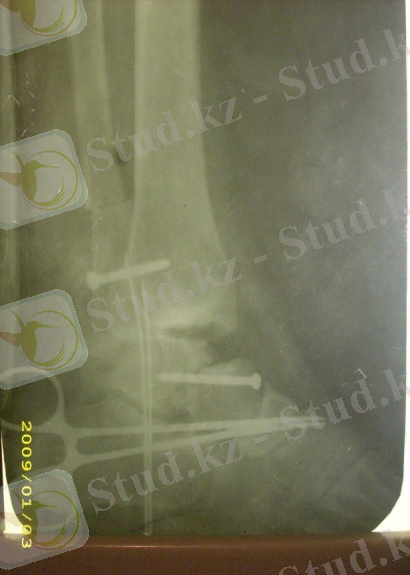

Егер жабық репозиция нәтиже бермесе ерте мерзімде (тиімді бірінші тәуліктерде) ашық репозиция және металлоостеосинтез (4-сурет) қолданылады.

4-сурет: Топай сүйегі мойнының ығысқан сынығы, винт арқылы остеосинтез кезіндегі рентгенограмма